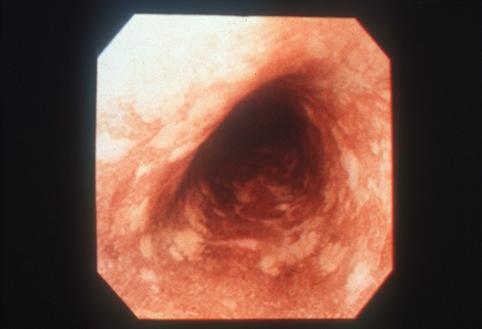

질환(병리주체)의 분류 악성 상피성종양/편평상피암

부위(장기별) 식도/중

검사방법 내시경

종양의 육안분류 0형(표재형)/IIc형(IIc)

종양의 최대경(밀리미터) 1~9

종양의 심달도 m

다발종양(동일 장기) 유(동시성)

다중종양(다수의 장기) 유(동시성)